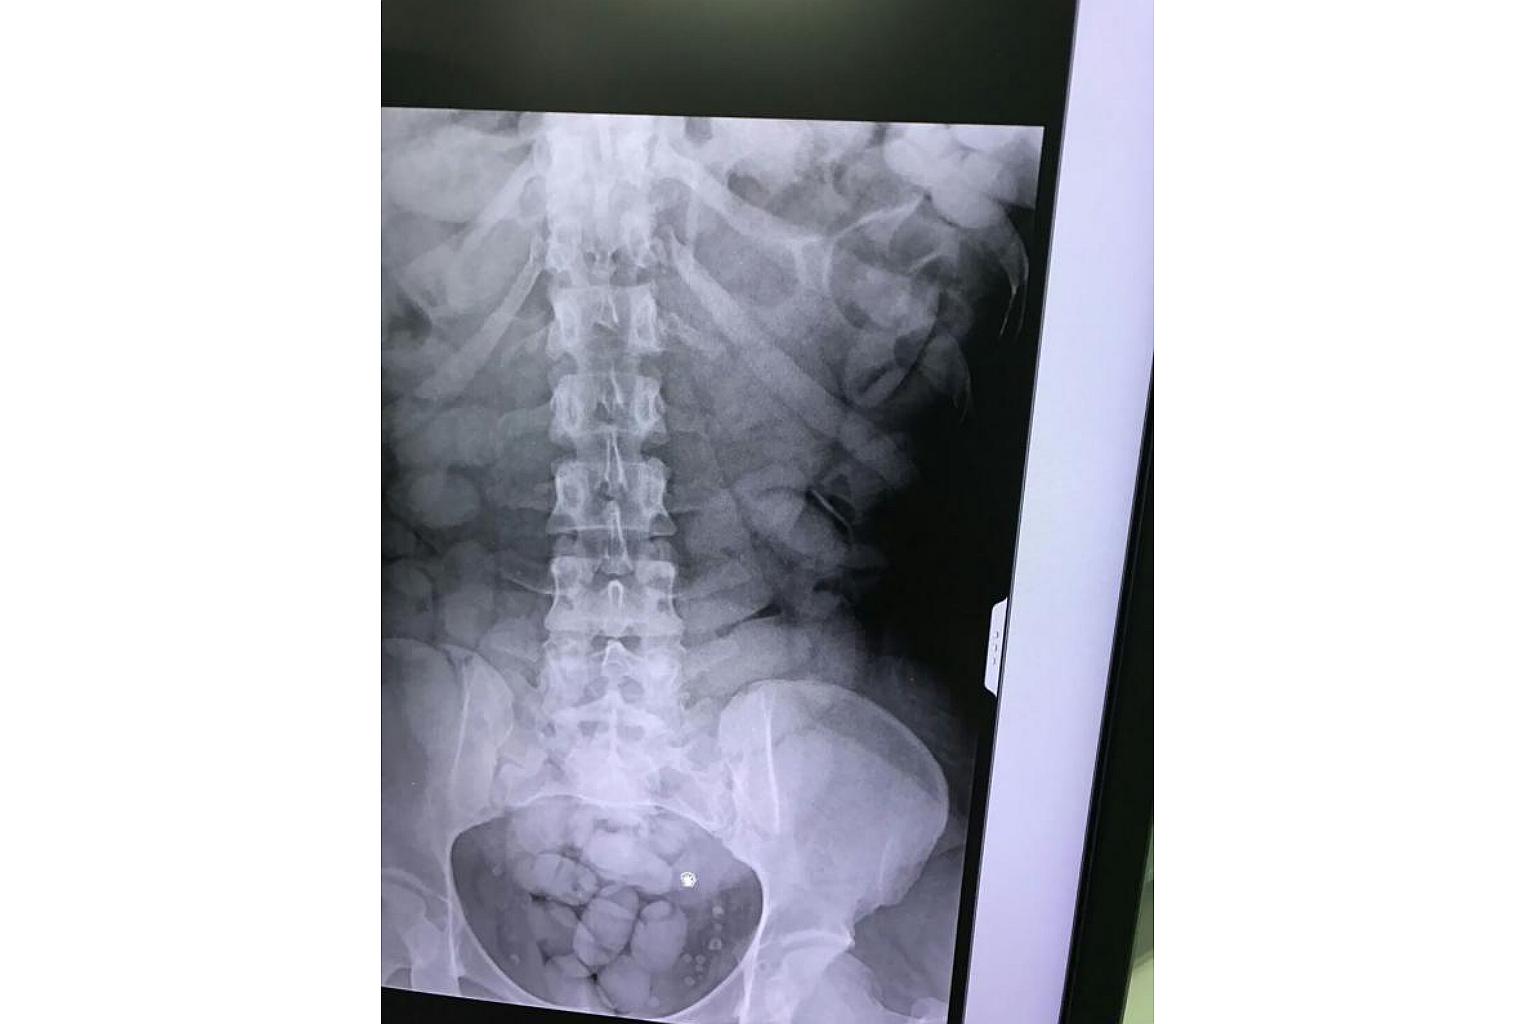

An airport X-ray revealed that the woman had more than 1kg of cocaine in her stomach wrapped in scores of small packets.

BANGKOK (AFP) - A 27-year-old woman from the Ivory Coast has been arrested on the Thai island of Phuket after an airport X-ray found more than 1kg of cocaine in her stomach wrapped in scores of small packets.

An X-ray revealed more than 60 small packages in her stomach, filled with 1.2kg of cocaine, according to Sirinya Sitdhichai, secretary-general of Thailand's Office of Narcotics Control Board.